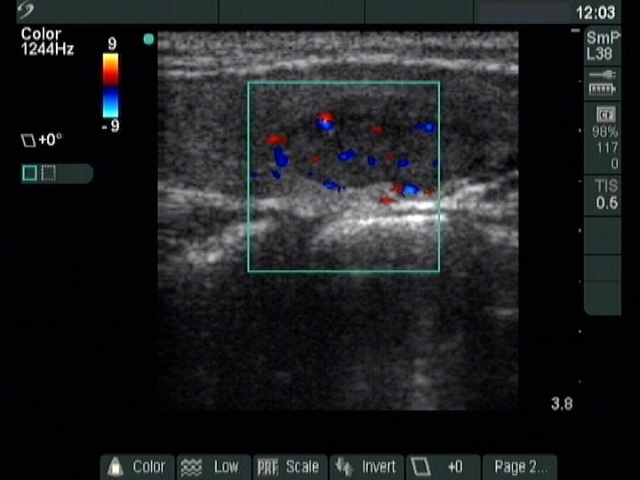

Ethanol sclerotherapy: thyroid cysts - Case 11

Three months after the sclerotherapy (ultrasonographic picture 3)

Left lobe, longitudinal scan, color Doppler mode. The nodule displays signs of perilesional and intralesional blood flow.